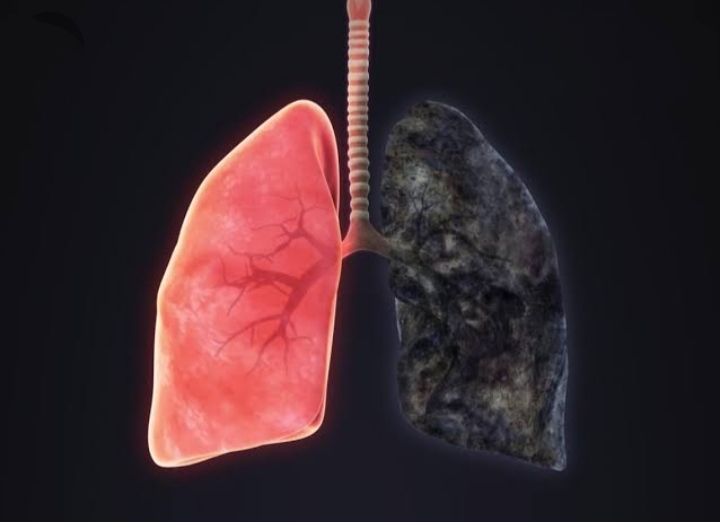

It is a long progressive disease of the lungs that primarily causes shortness of breath, due to over inflation of the alveoli.

Emphysema is included in group in a group is called COPD

Smoking

Pathophysiology :

1 . breakdown of bronchioler walls

2 . Enlarged bronchiols

3 . Few and large damaged sac

4 . Result reduced surface area for exchange of oxygen in blood

5 . It is a permanent non reversible change

6 . Reduce respiratory functions

7 . Sacs are destroyed and narrowed

Finally lungs have a irreversible disease condition,…..